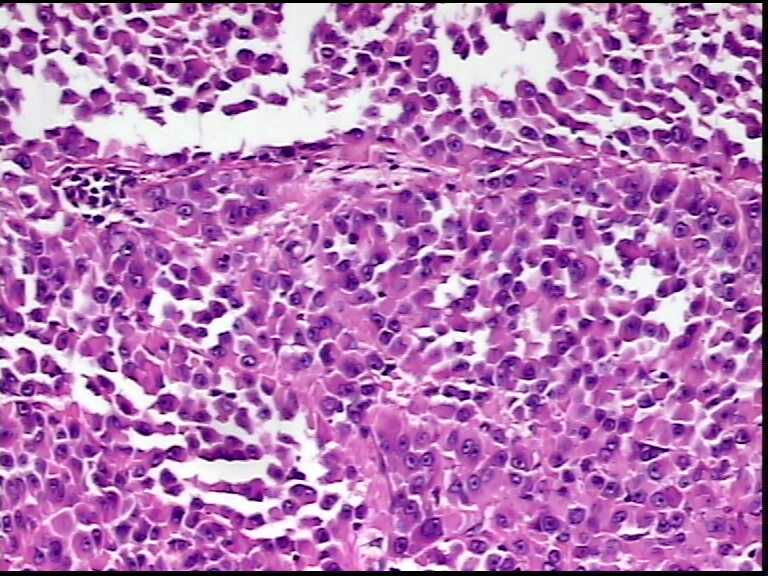

患者男性,34岁,临床没给提供,该患者梅毒阳性

• 请各位老师会诊一下 颌下淋巴结图1

图1

颌下淋巴结肿大,送检肿物直径2.5cm,切面灰粉色,质地嫩,先做了个LCA瘤细胞阴性

形态符合霍奇金淋巴瘤(看到比较典型的R-S细胞)。

淋巴结内见大量宽而嗜酸性胞浆的肿瘤细胞,瘤细胞核大,偏心分布,核仁明显,成上皮样表现,部分似有腺泡样排列,符合淋巴结转移性恶性肿瘤,首先除外转移癌,恶性黑色素瘤,继而除外浆细胞瘤(岁数不太符合),横纹肌肿瘤等。

淋巴结内见大量宽而嗜酸性胞浆的肿瘤细胞,瘤细胞核大,偏心分布,核仁明显,成上皮样表现,部分似有腺泡样排列,符合淋巴结转移性恶性肿瘤,首先除外转移癌,恶性黑色素瘤,继而除外浆细胞瘤(岁数不太符合),横纹肌肿瘤等。同意楼上的观点。